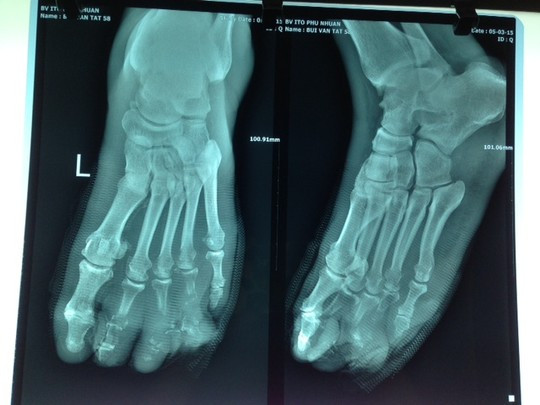

Bệnh viện Sài Gòn ITO cho biết nơi đây vừa tiếp nhận phẫu thuật loại bỏ hoại tử lan rộng thành công cho bệnh nhân Bùi Văn T. (58 tuổi, ngụ An Giang) do bị mắc bệnh tiểu đường mà không biết.

Trước đó, ngày 5-3, ông T. nhập viện với bàn chân chân trái nhiễm trùng nặng, các ngón chân số 2, 3, 4 đang bị hoại tử. Do vết nhiễm trùng quá nặng và bị hoại tử đến xương, mô dưới da, bao gân gập duỗi các ngón lan dọc đến tận giữa bàn chân nên các bác sĩ quyết định phải tháo khớp nửa bàn chân để tránh nguy cơ nhiễm trùng có thể tái phát và lan rộng cho bệnh nhân.

Chỉ vì chủ quan, bệnh nhân phải chịu cảnh tháo khớp bàn chân.